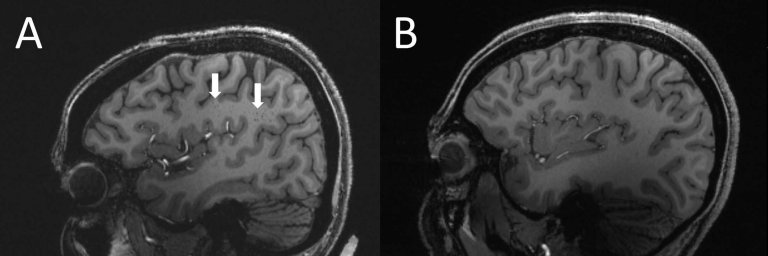

"Os dados sugerem que ambos os distúrbios da dor de cabeça são altamente circadianos em vários níveis, especialmente a cefaleia em salvas," disse o Dr. Mark Burish, da Universidade do Texas (EUA). "Isso reforça a importância do hipotálamo - a área do cérebro que abriga o relógio biológico primário - e seu papel na cefaleia em salvas e na enxaqueca. E também levanta a questão da genética dos gatilhos, como alterações do sono, que são gatilhos conhecidos para enxaqueca e são pistas para o ritmo circadiano do corpo."